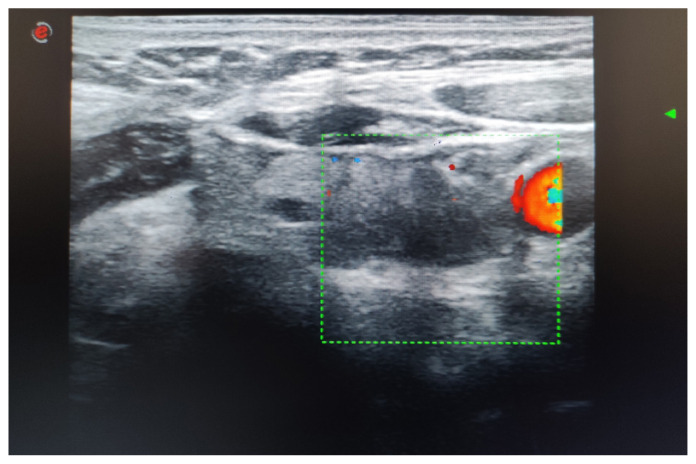

Materials and methods: A 45-year-old woman who had previously experienced high levels of calcium in her blood and abnormally elevated parathyroid hormone levels underwent surgical removal of the left parathyroid gland. Following surgery, she exhibited high levels of parathyroid hormone along with normalized calcium levels and persistent fatigue. Ultrasound imaging showed a hypoechoic mass on the left side, which was initially considered to be a recurrent parathyroid tumor.

Results: A comprehensive assessment, including neck CT scans and fine needle aspiration cytology, revealed that the mass was actually residual surgical cellulose, making diagnosis more challenging due to vitamin D deficiency.